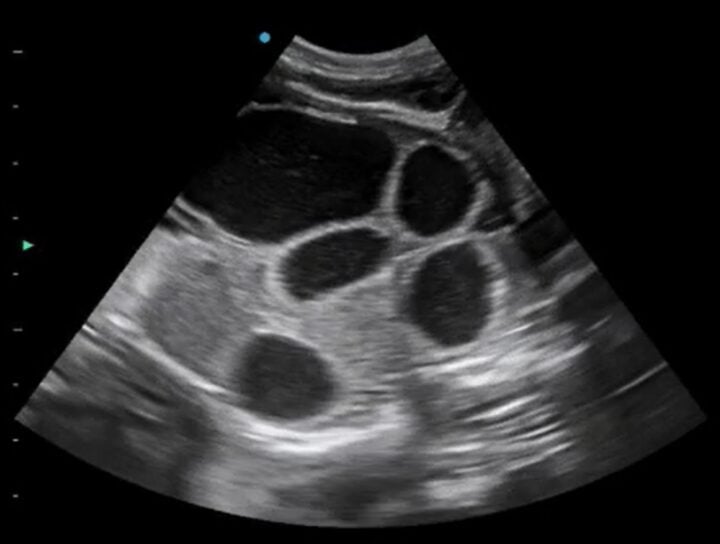

Intestines or gestation sacs? Manipulating the imaging plane

Once you have identified and looked around the bladder and as you begin to move your transducer cranially, you will encounter either more gestation sacs or the intestines (Figure 2) in the “normal” bitch or queen. Intestines are one of the great pitfalls of pregnancy scanning and are mistaken for gestation sacs more often than you might care to believe. The key is to rotate your transducer 90 degrees to confirm whether the circular structure you are seeing is indeed spherical (ie an early gestation sac).

Manipulating your imaging plane is essential for certain measurements, such as crown–rump length and biparietal diameter. Still images can be ambiguous – Figure 3, for example, is not pregnancy – so watching a video clip (Video 1) instead makes this image more interpretable.